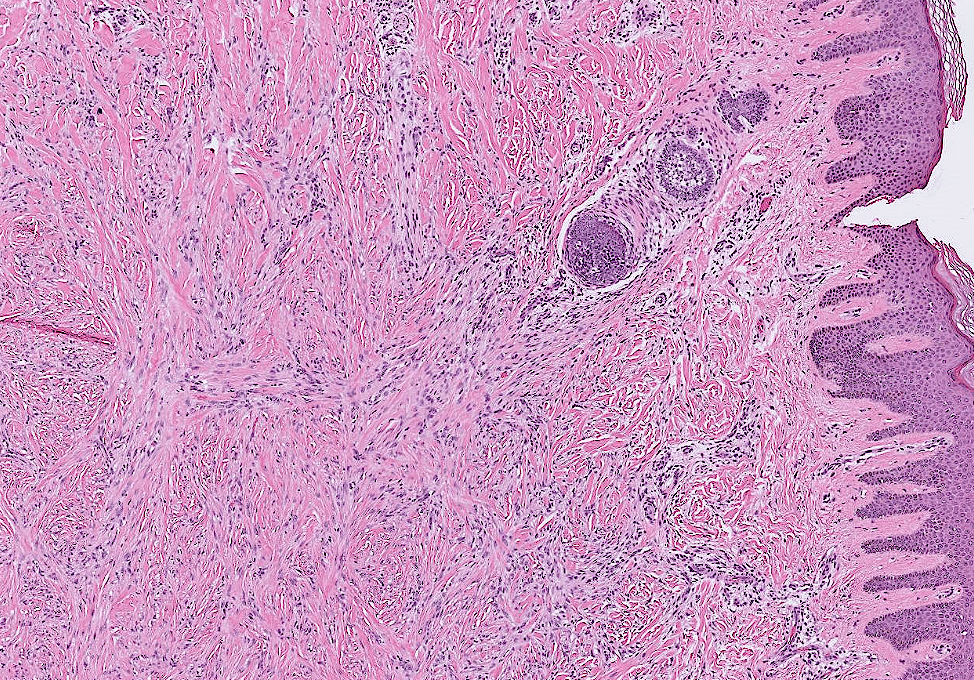

endometrial cancer